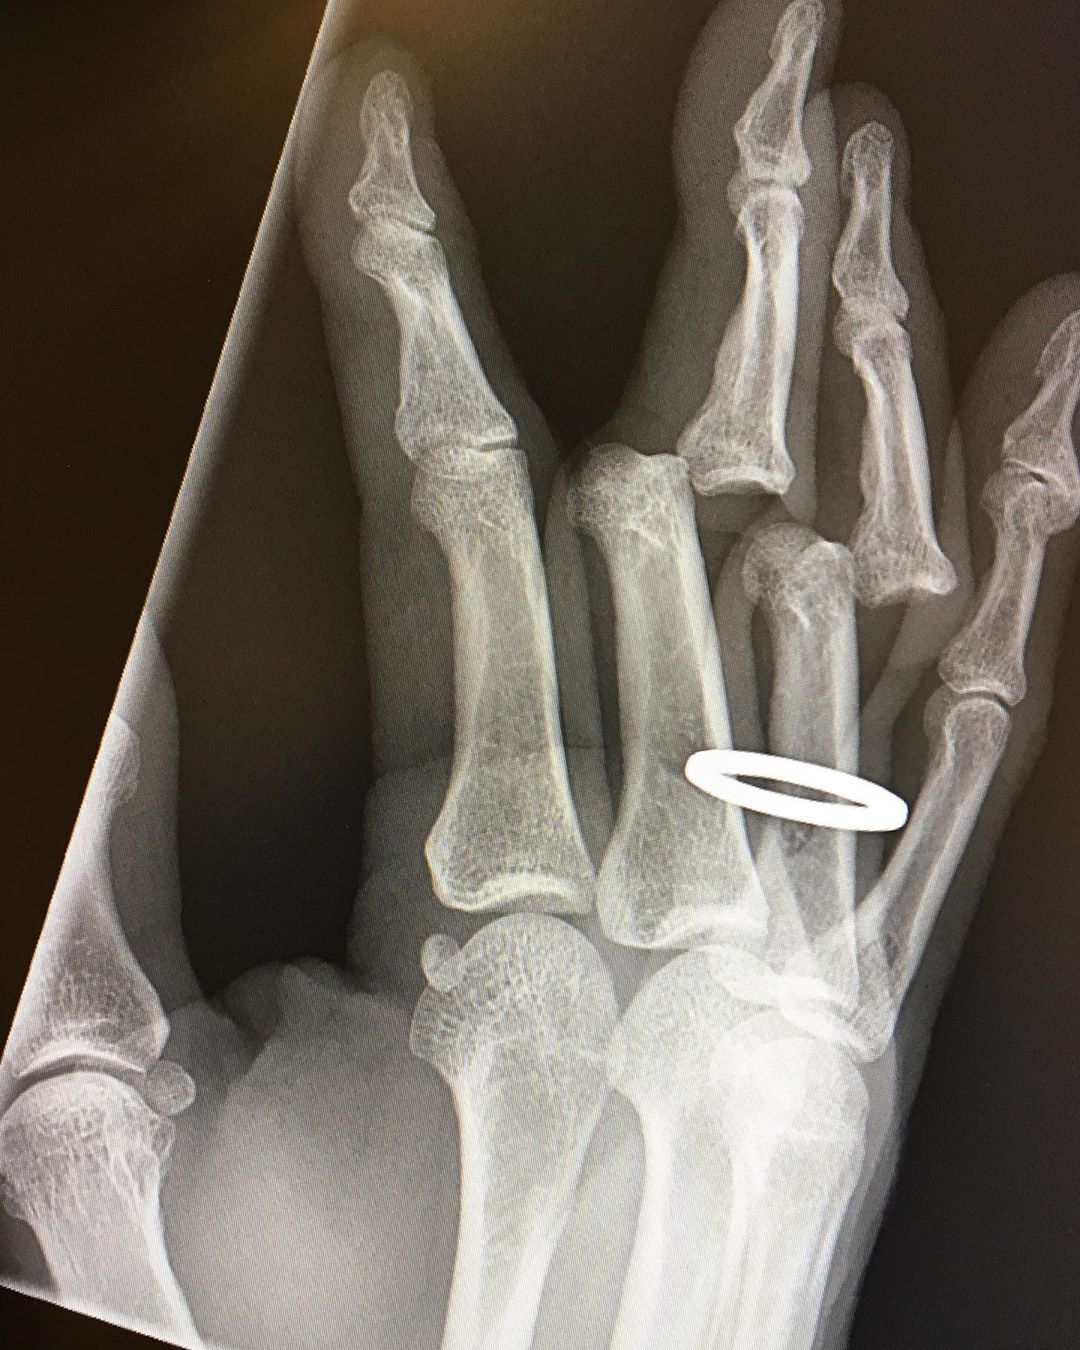

Noticias Tony Hawk publicó su impresionante lesión en la mano El skater más famoso del mundo aseguró que “tuvieron que cortarme el anillo de boda" por la lesión. Por Diego Puebla Hernández | 11 Jun, 2020. 10:56 hrs El skater más famoso del mundo aseguró que “tuvieron que cortarme el anillo de boda» por la lesión. Tony Hawk, compartió unas impactantes imágenes de una lesión que sufrió tras una fuerte caída patinando. A través de su cuenta de Instagram, el estadounidense de 52 años compartió el fin de semana unas fotos en urgencia con sus dedos fracturados, y ahora mostró nuevas imágenes. “Acabo de recibir mis radiografías. Tuvieron que cortarme el anillo antes de devolver mis huesos a su posición vertical”, escribió en la red social. Agregando que “todavía están adoloridos, rígidos e hinchados, pero los puedo usar. Y todavía amo mi trabajo“. Hawk explicó en otra publicación que tuvo el accidente cuando realizaba piruetas junto a sus hijos en una piscina vacía. “La piscina era pequeña y no usé protecciones completas. La sesión fue divertida hasta que de repente me encontré en el fondo de la piscina con los dedos doblados en nuevas direcciones. Fue entonces cuando lamenté no usar todas las protecciones”, contó. Revisa aquí las imágenes. ¡Advertencia! Pueden ser perturbadoras para algunas personas: Ver esta publicación en Instagram We had a chance to skate a legendary backyard pool yesterday thanks to @ozzie_ausband, so I brought my oldest son Riley and our friend Chris. I rarely get to skate with Riley anymore because we ride different terrain, and lately we are both busier than ever trying to run businesses in the most challenging of times. Ozzie invited Eddie Elguera (a childhood hero) to join, so our crew spanned three generations of skateboarding. I joked that Eddie is the reason Riley grabs his nose on backside airs because I learned that technique by watching him, and Riley learned it by watching me. The pool was smaller than I anticipated so I didn’t wear full pads, likening it to a miniramp. We were having a blast, and at one point I actually gave advice to Eddie on doing a frontside rock (one of his signature tricks, and my first “advanced” move as a kid). The session was fun until I did a backside smith stall as a set up for a backside blunt, and suddenly found myself on the flat bottom with my fingers bending in new directions. The coping was huge and I paid the price by hanging up on my back truck. In that moment, I regretted not wearing full pads. Ironically, that wouldn’t have saved me from injury but I was being too cavalier to think that a wall over 8’ with vert was as “safe” as a mini-ramp. The session came to a screeching halt, and Riley drove me to the hospital like Ricky Bobby with a cougar in the backseat. Upon being admitted, a nurse checked my fingers and said they looked “dusky.” That expedited my care, and I was immediately assigned to a room as an x-ray machine arrived. Apparently, “dusky” is the color of extreme circulation loss. Within 30 mins, my fingers were back in place, and no longer dusky. I write this because today I am filled with divergent emotions: sadness from scaring my son & friends, regret from being cocky / careless, grateful from having an injury that could have been worse, and frustrated that I never got a backside blunt… as my skater ego endures. As pro skaters, we accept that injuries are inevitable and perseverance is key to success. But it still sucks to get hurt, especially at my age. And I’ll still be back for more 📷 @williamsharpimages Una publicación compartida por Tony Hawk (@tonyhawk) el 7 de Jun de 2020 a las 12:46 PDT deportes tony hawk Otros más: Festivales Coachella y Stagecoach 2020 son cancelados Las baterías ‘infinitas’ para autos eléctricos que duran 16 años Sigue a FUTURO.cl en Google Discover Recibe nuestros contenidos directamente en tu feed. Seguir en Google Contenido patrocinado